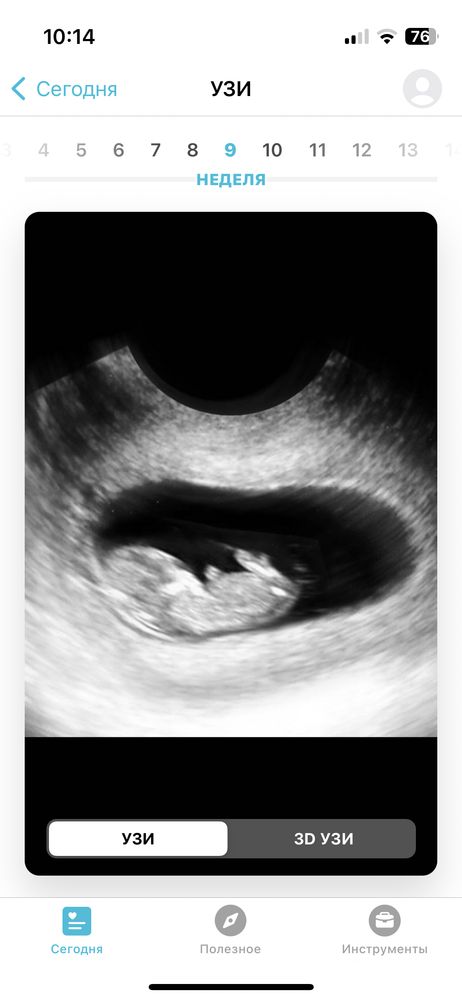

Виктория, ИзображениеЭто 10 недель, он просто лежит и уже смахивает на человека , но не видно хорошо пальчиков и всего остального. Изображение Это с приложения 9 недель , вы видите пальчики на руках??? Я с вами спорить не буду , более информативно смотреть когда больше 11